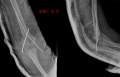

骨化性肌炎